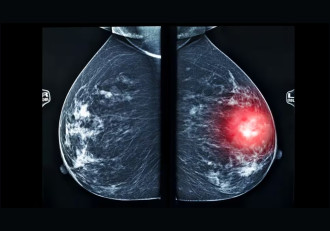

Breast cancer screening plays a central role in reducing mortality, yet current screening methods face several practical and clinical limitation1